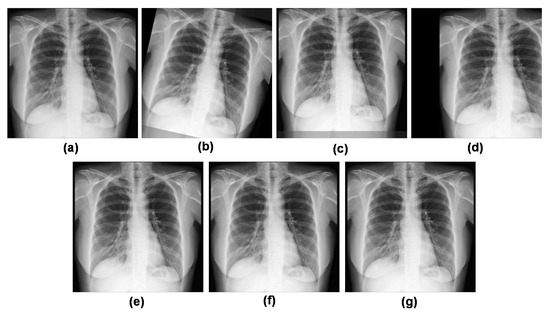

3.4. Data Pre-Processing